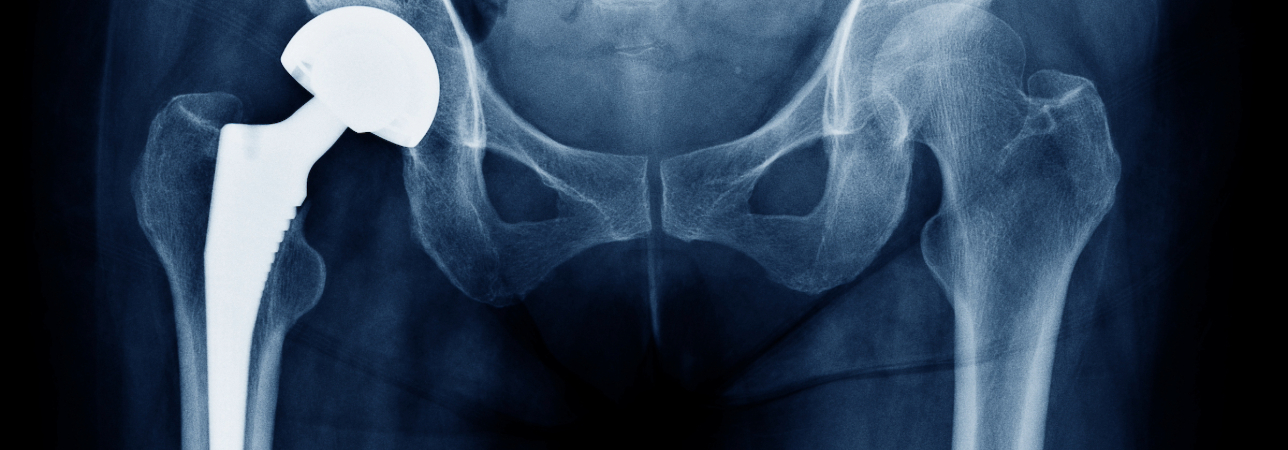

Il Dr. med. Mauro Molina, specialista in chirurgia ortopedica e traumatologia dell’apparato locomotore, membro FMH, ci parla della chirurgia di revisione protesica, il cui scopo è quello di fornire supporto ai pazienti che sono andati incontro a un fallimento parziale o totale di un impianto protesico effettuato in precedenza.

«L’intervento di artroprotesi consiste come è noto nel sostituire le strutture anatomiche dell’anca o del ginocchio, ormai danneggiate, con l’impianto di componenti meccaniche che permettono di restituire all’articolazione la sua funzionalità e risolvere il dolore. Con l’evoluzione dei materiali e delle tecniche chirurgiche si è assistito ad un significativo aumento di sopravvivenza degli impianti nel tempo. In particolare, oggi le nuove superfici delle protesi permettono una migliore fissazione all’osso, il polietilene di nuova generazione ha un’usura minore rispetto a quello usato in precedenza, e la ceramica per uso biomedico ha una resistenza maggiore; i nuovi accoppiamenti polietilene/ceramica, e ceramica/ceramica hanno un bassissimo coefficiente di usura ed hanno contribuito a conferire all’impianto una sopravvivenza più lunga.»